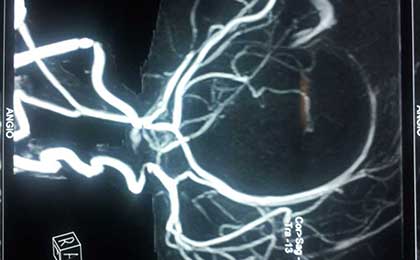

MRA

• MRA